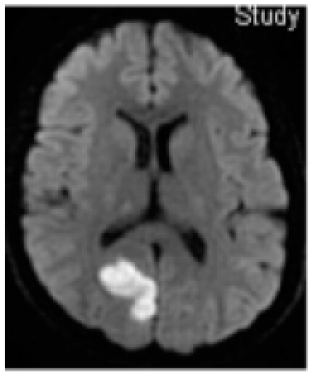

¿Qué podemos encontrar en neuroimágenes?

Mayor incidencia de lesiones inespecíficas (gliosis) de sustancia blanca (12 -47%).

• 11% en la cuarta década

• 83% en la séptima década